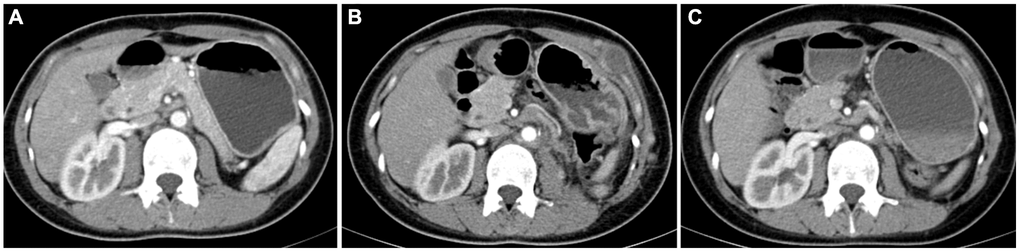

A total of 24 patients received postoperative medication-assisted therapy in the Ta cohort; six received mTOR inhibitor therapy, and 24 received TKI therapy. Due to TKI treatment failure, six patients chose an mTOR inhibitor. Progression was significantly controlled after the treatment procedure was replaced in five patients, while one did not experience an obvious treatment effect. Two patients were treated with a combination of TKI and mTOR inhibitor, but they abandoned the combination therapeutic procedure because of early side effects and continued the monotherapy therapeutic procedure (Figure 6).

Figure 6. Contrast-enhanced computed tomography results of postoperative follow-up in a patient with TFE3-RCC. (A) The results of re-examination one month after the surgery; (B) three months after surgery, the patient’s re-examination showed multiple tumor metastases in the abdominal wall, left psoas major muscle, and pelvic cavity, so the patient started sunitinib therapy; (C) the re-examination results at six months after surgery showed that the metastasis was smaller than before, and the disease progression was controlled.